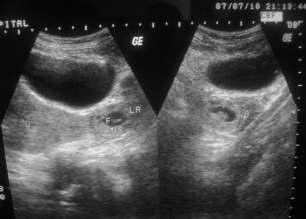

Ararecaseofrecurrent(consecutive)ectopicpregnancywithfibroiduterus

— Owvass Hamied Dar, Maqsood Ahmad Dar, Ghanshyam, Pankaj Sharma ....................................72